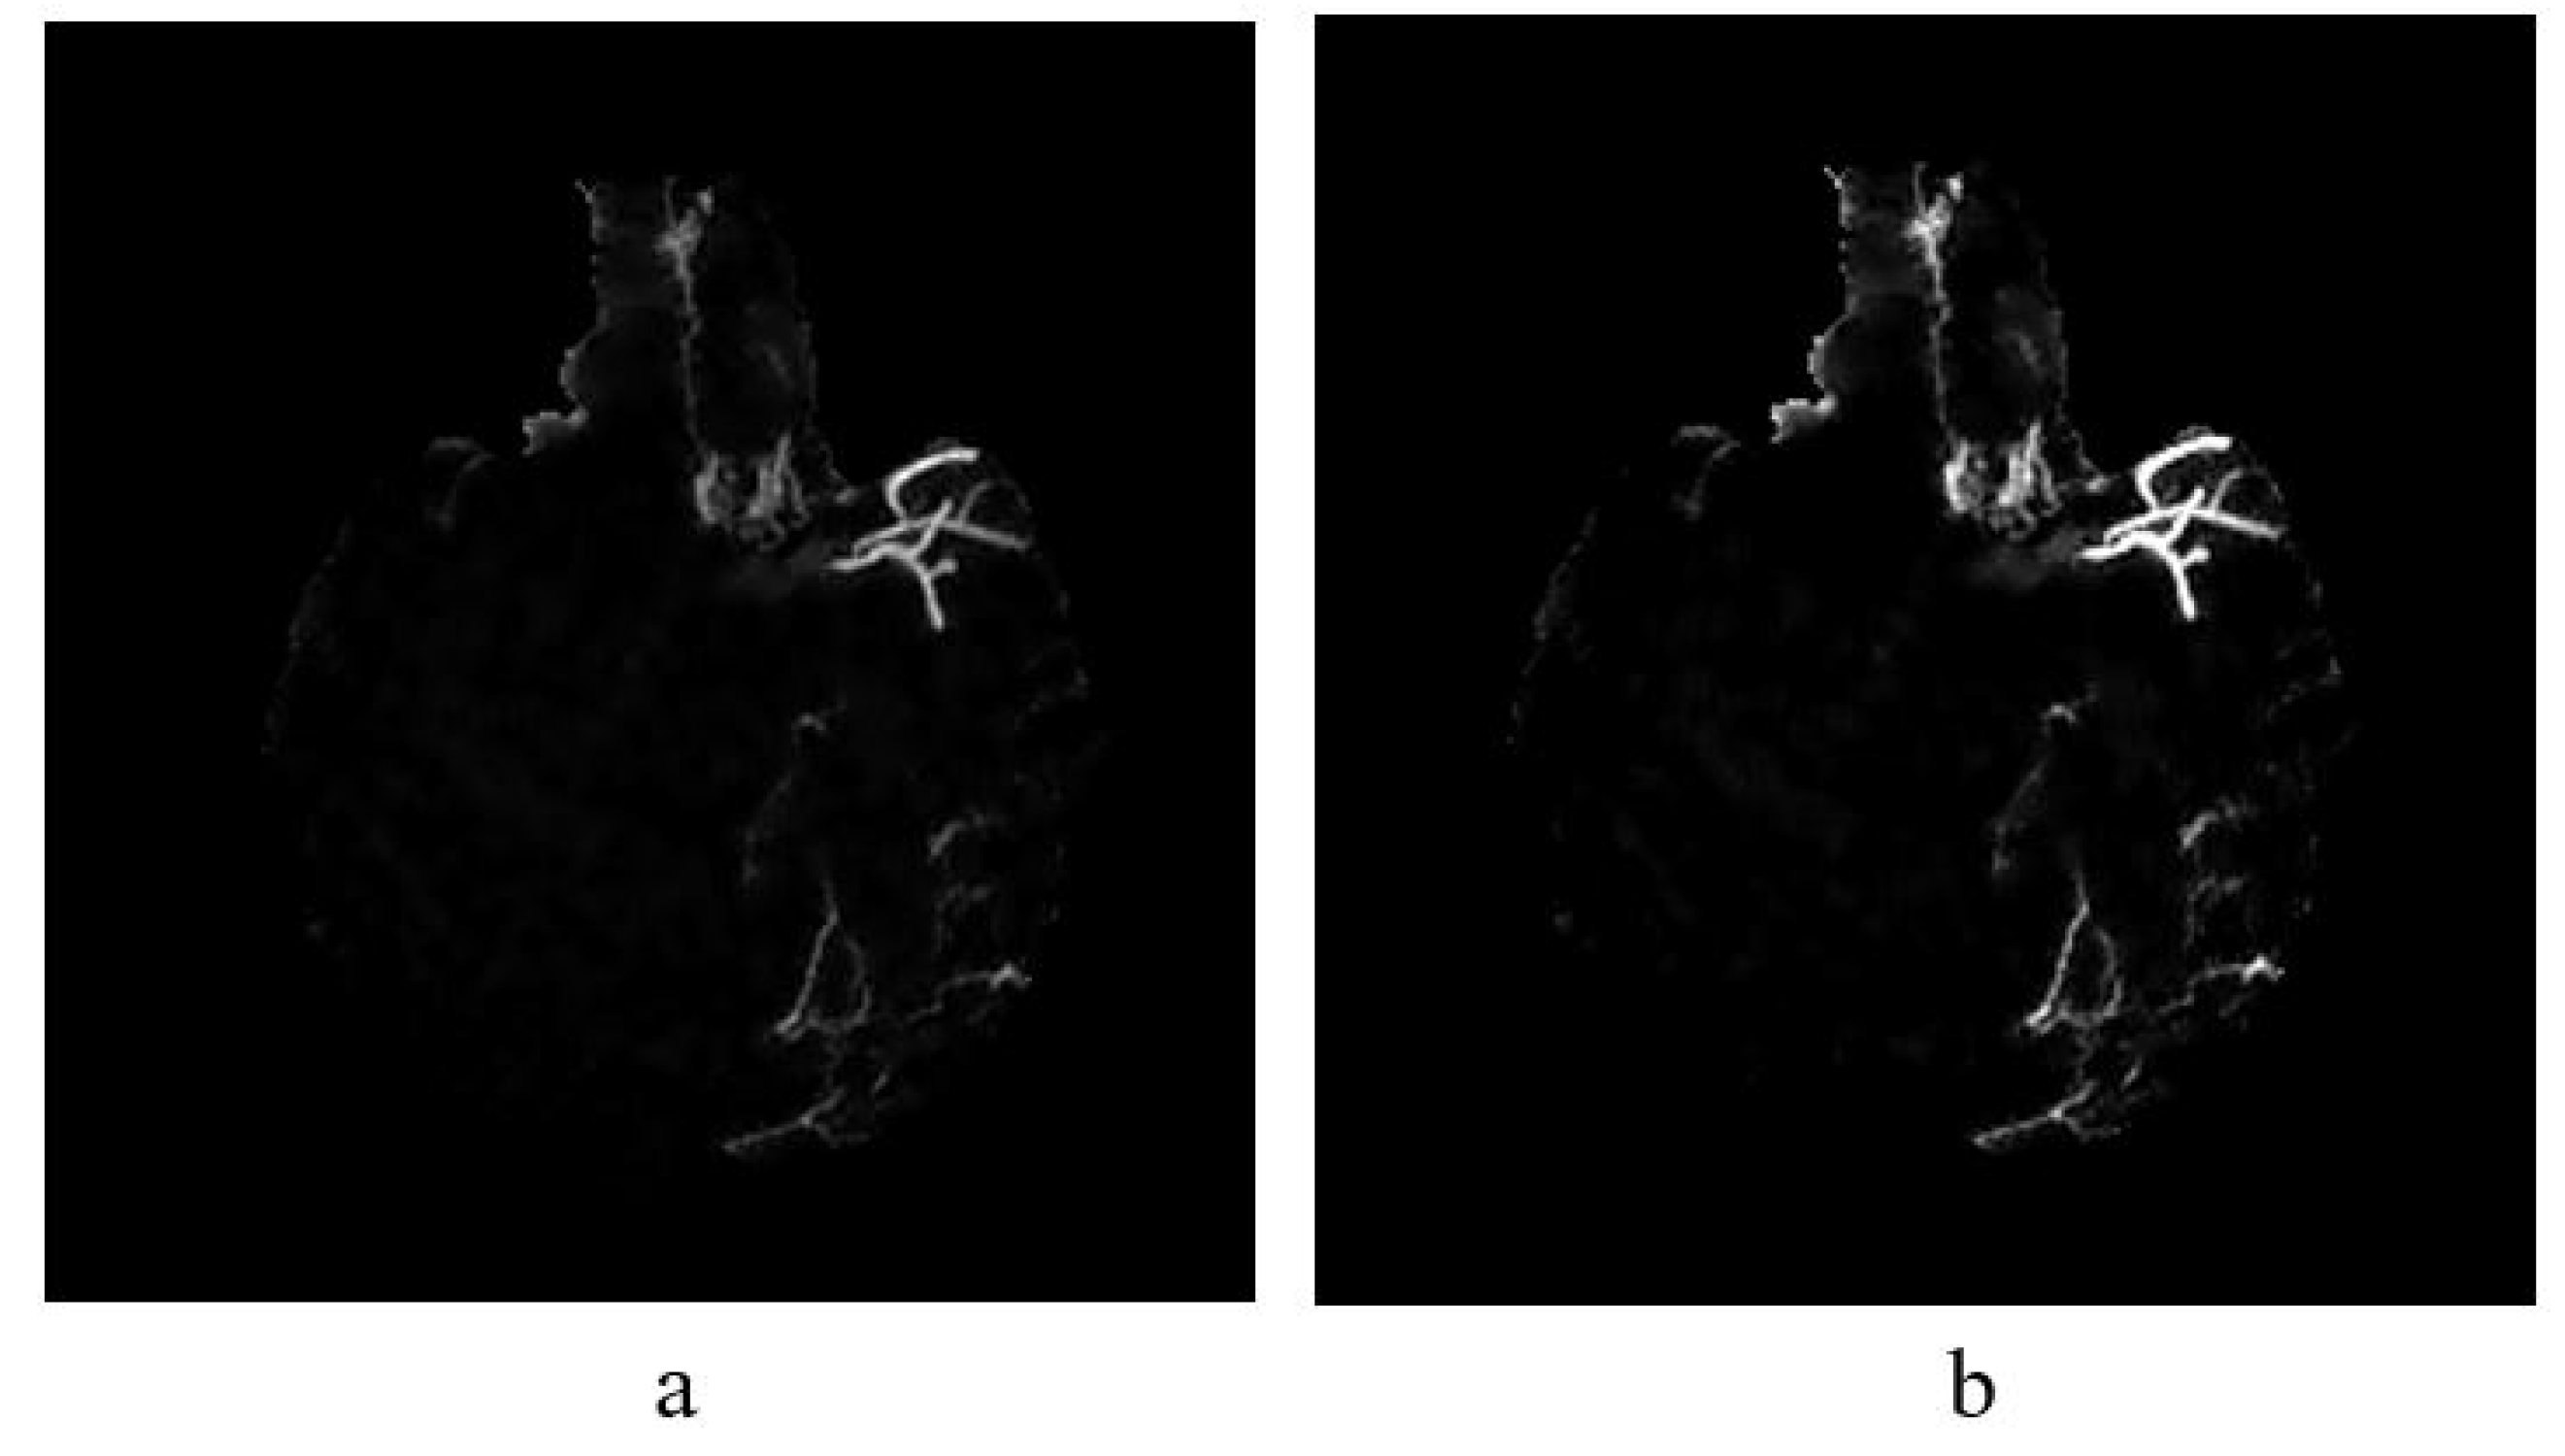

4.1. HU Conversion and MIP Projection

The regression model is used to estimate the regression coefficient to obtain the most promising image for further analysis. By implementing the linear equation in Equation (1), we can control the parameters of w and m to obtain the output that we desire. The linear function can be used to convert pixel values from the CBCT scanner to CT values using the Equation (2). As illustrated in Figure 6, if a CBCT image is converted to HU without adjusting the brightness component by multiplication with the output of Equation (20), we will lose the information of the blood vessels in MIP image.

where Q indicates pixel value in CBCT.

Figure 6.

MIP image (a) without brightness adjustment prior to HU conversion in comparison to (b) with brightness adjustment prior to HU conversion.

MIP image (a) without brightness adjustment prior to HU conversion in comparison to (b) with brightness adjustment prior to HU conversion. As shown in Figure 6b, some vessel information is preserved as compared to that of Figure 6a. Therefore, it is necessary to perform brightness adjustment before converting the image into HU. The conversion is applied for each slice before performing the maximum intensity projection. Then, skull removal will be carried out to obtain MIP images without the skull as shown in Figure 4e.